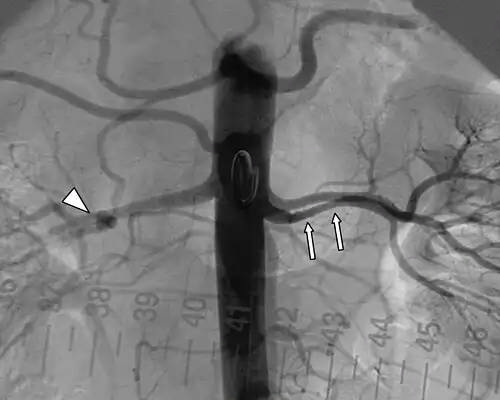

آنوریسم. آنوریسم یا رگ برآمدگی ( به انگلیسی: Aneurysm ) برگرفته از ἀνεύρυσμα یونانی به معنای فتق شریان است. اگرچه ممکن است آنوریسم در هر رگی رخ دهد، اما نمونه های کشنده آن آنوریسم حلقه های ویلیس کف مغز، آنوریسم آئورت و آنوریسم آئورت شکمی هستند. آنوریسم ها می توانند به دنبال سکته قلبی در خود قلب ایجاد شوند، مانند آنوریسم های بین بطن و دهلیز.

ضعف دیوارۀ سرخرگ که باعث «بیرون زدگی۱» آن می شود. در این حالت خطر پاره شدن و درپی آن خون ریزی شدید وجود دارد. این خون ریزی شدید اغلب منجر به مرگ می شود. در صورت تشخیص به موقع، برخی آنوریسم های قابل دسترسی را می توان با عمل جراحی درمان کرد اما چنین عمل وسیعی برای بیمارانی که وضع سلامتی مناسبی ندارند پُرخطر است. پارگی شریان آئورت سالانه باعث بیش از ۱۰هزار مورد مرگ در انگلستان می شود. در ۱۹۹۵ جراحان بریتانیایی روشی ابداع کردند که در آن، با واردکردن یک سوند۲ از ناحیه کشاله ران به سیستم سرخرگی و آئورت، یک وصله۳ پلی استری در محل آنوریسم قرار می دهند. این وصله با استفاده از یک «آلیاژ حافظه دار۴» که در دمای بدن شکل اصلی را به خود می گیرد، تقویت می شود. وقتی وصله در محل مناسب قرار گرفت، سوند خارج شده وصله منبسط می شود و با فشار آوردن بر دیوارۀ آئورت در محل خود قرار می گیرد. ممکن است در آینده این عمل با بیهوشی موضعی انجام شود.

همچنین استفاده از رگ‌نگاری مخ امکان درمان فوری را نیز فراهم می‌کند. برای مثال، پس از شناسایی آنوریسم، می‌توان از کاتتری که به منظور رگ‌نگاری کارگذاشته شده استفاده نمود و سیم‌های فلزی ویژه ای را از درون آن به ناحیهٔ آنوریسم رساند که پس از مدتی طولانی منجر به رشد بافت همبند در منطقه و تقویت دیوارهٔ رگی می‌گردد.